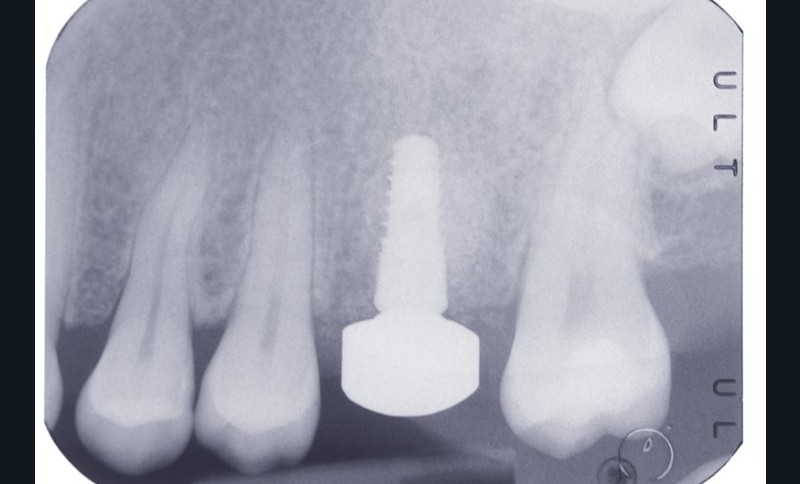

Après trois mois, un implant Naturall+, de diamètre 4 x 10 mm, est posé en remplacement de la 26. La stabilité primaire mesurée au moment de la pose de l’implant est supérieure à 35 N.cm.

Après la pose de l’implant, la stabilité primaire autorise la mise en place d’un pilier de cicatrisation. L’implant Naturall+ permet de choisir dans une sélection de 9 formes anatomiques de pilier de cicatrisation (3 profils et 3 hauteurs) (fig. 2 et 3).

Pour fixer le pilier de cicatrisation, une interface Esthetibase est posée sur l’implant. Il existe de nombreuses interfaces permettant de s’adapter à la plupart des marques d’implants sur le marché. Le pilier iphysio® C1 choisi est clipsé sur l’interface (fig. 4).

Après 4 mois d’ostéointégration de l’implant, les tissus mous sont parfaitement stables autour du capuchon. Après…